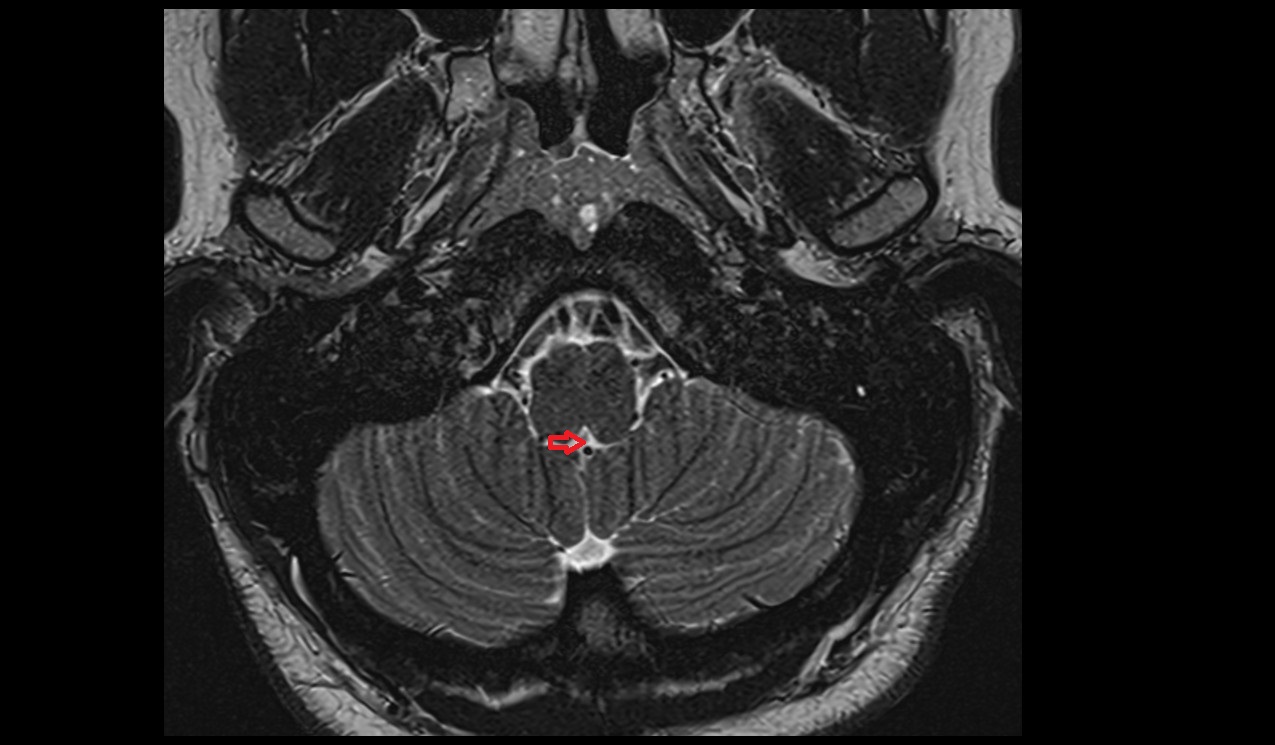

- Cerebellum

- Flocculus

- Crus I of ansiform lobule of cerebellum

- Crus II of ansiform lobule of cerebellum

- Paramedian lobule (HVII) of cerebellum

- Simple lobule (HVI) of cerebellum

- Anterior quadrangular lobule (HV) of cerebellum

- Anterior quadrangular lobule (HlV) of cerebellum

- Biventral lobule (HVIII) of cerebellum

- Central lobule (II & III) of Cerebellum

- Culmen (IV, V) of Cerebellum

- Declive (VI) of Cerebellum

- Cerebellar tonsil (H IX)